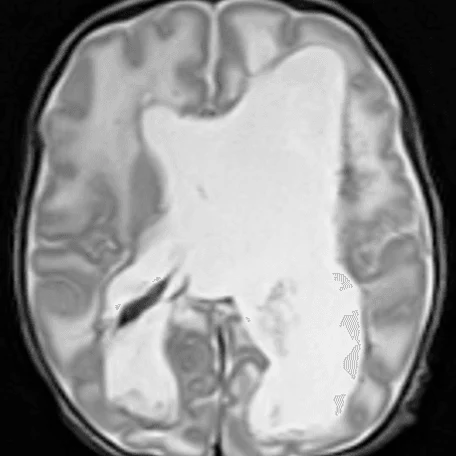

Внутрижелудочковые кровоизлияния

Чаще возникают у недоношенных новорожденных. Основным источников ВЖК служат сосуды эпендимы мозга и сосудистые сплетения. Способствующие факторы: затяжные или быстрые роды, перинатальная гипоксия, коагулопатии, нестабильность гемодинамики у новорожденного.